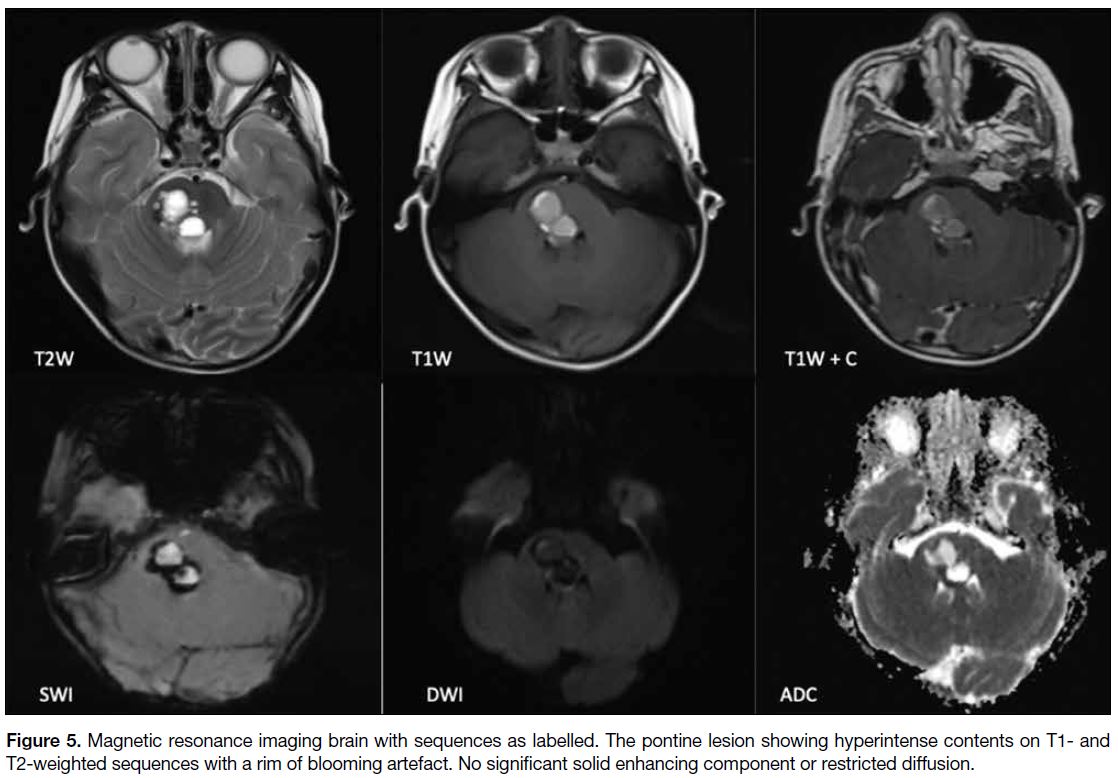

blood product or calcification (Figure 4). MRI was performed shortly afterwards, and the lesion appeared

predominantly hyperintense on T1- and T2-weighted

images with internal dependent hypointense contents.

No significant solid enhancing component was seen

(Figure 5). The initial imaging differentials considered

were brainstem gliomas, possibly complicated with

haemorrhage, or lesions that contain calcification,

including ganglioglioma, rosette-forming glioneuronal

tumour, or pilocytic astrocytoma.

Figure 5. Magnetic resonance imaging brain with sequences as labelled. The pontine lesion showing hyperintense contents on T1- and T2-weighted sequences with a rim of blooming artefact. No significant solid enhancing component or restricted diffusion.